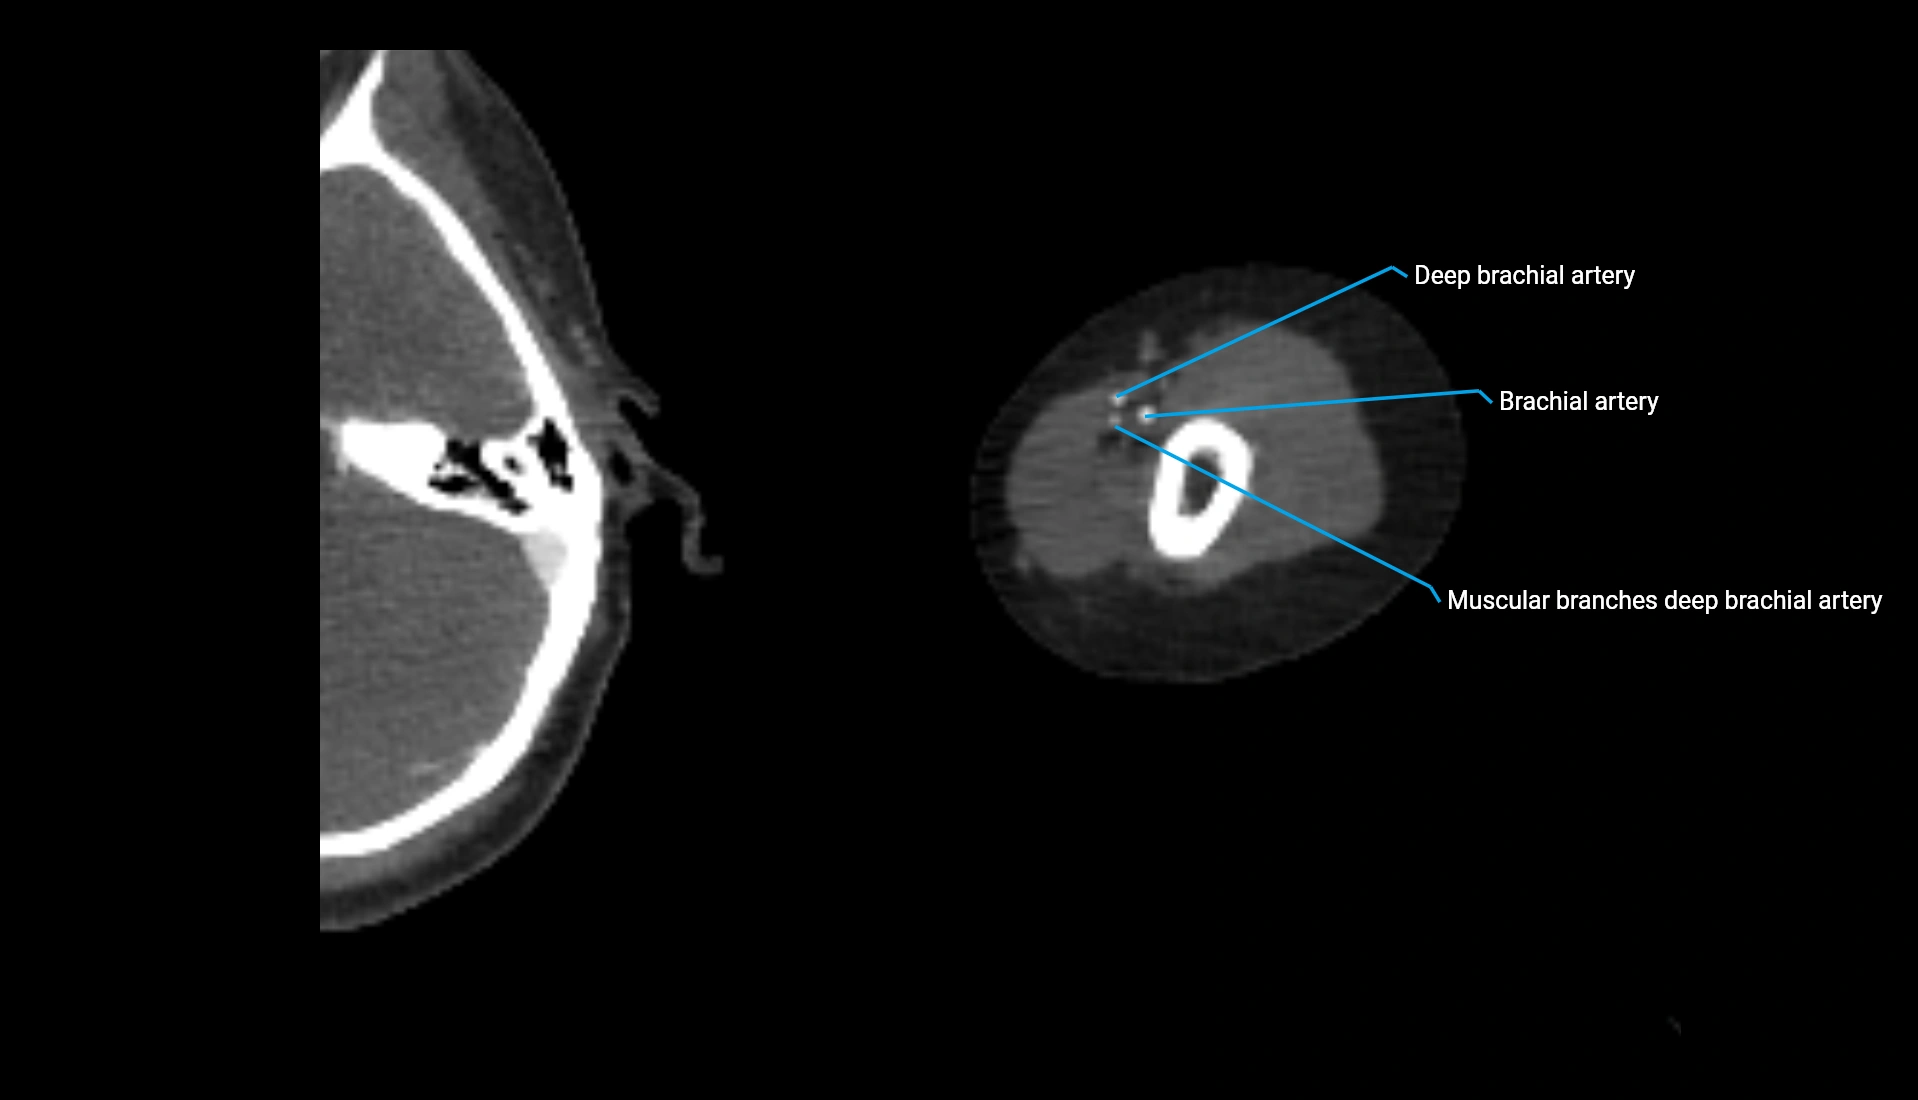

CT Appearance

Non-Contrast CT:

• Cortex: High-density, sharply defined

• Subchondral bone: Dense cancellous matrix

• Articular surface: Smooth concave contour articulating with the capitellum

• Excellent for evaluating bone integrity, alignment, and subtle fractures

Post-Contrast CT:

• Bone: No enhancement

• Joint capsule and synovium: Mild enhancement outlining the joint

• Improves contrast between soft tissues and bony margins

• Useful in detecting subtle joint abnormalities or postoperative changes